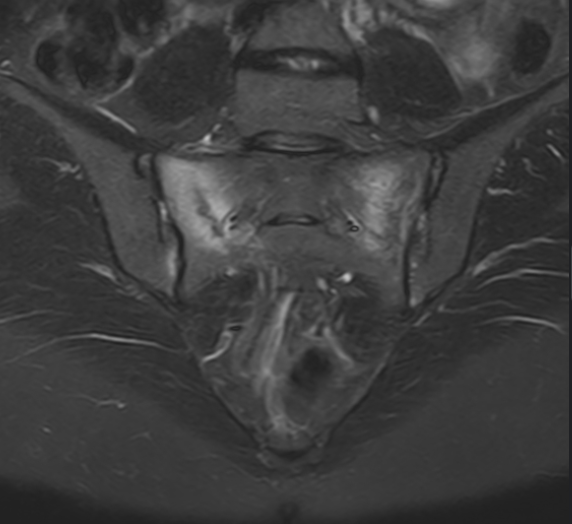

Typically the presentation is low back / pelvic pain, usually it can be localised to the junction of the pelvis and the spine, worsening with activity. Groin pain and even sciatica pain can occur. MRI diagnoses a crack, or cracks in the pelvis. It can occur in osteoporosis, vitamin D insufficiency, possibly over hormone imbalances, possibly also as an athletic overuse injury (where it is usually called a stress fracture). Screw fixation, and sacroplasty (injecting bone cement) are higher risk, and probably lower success than medical management.